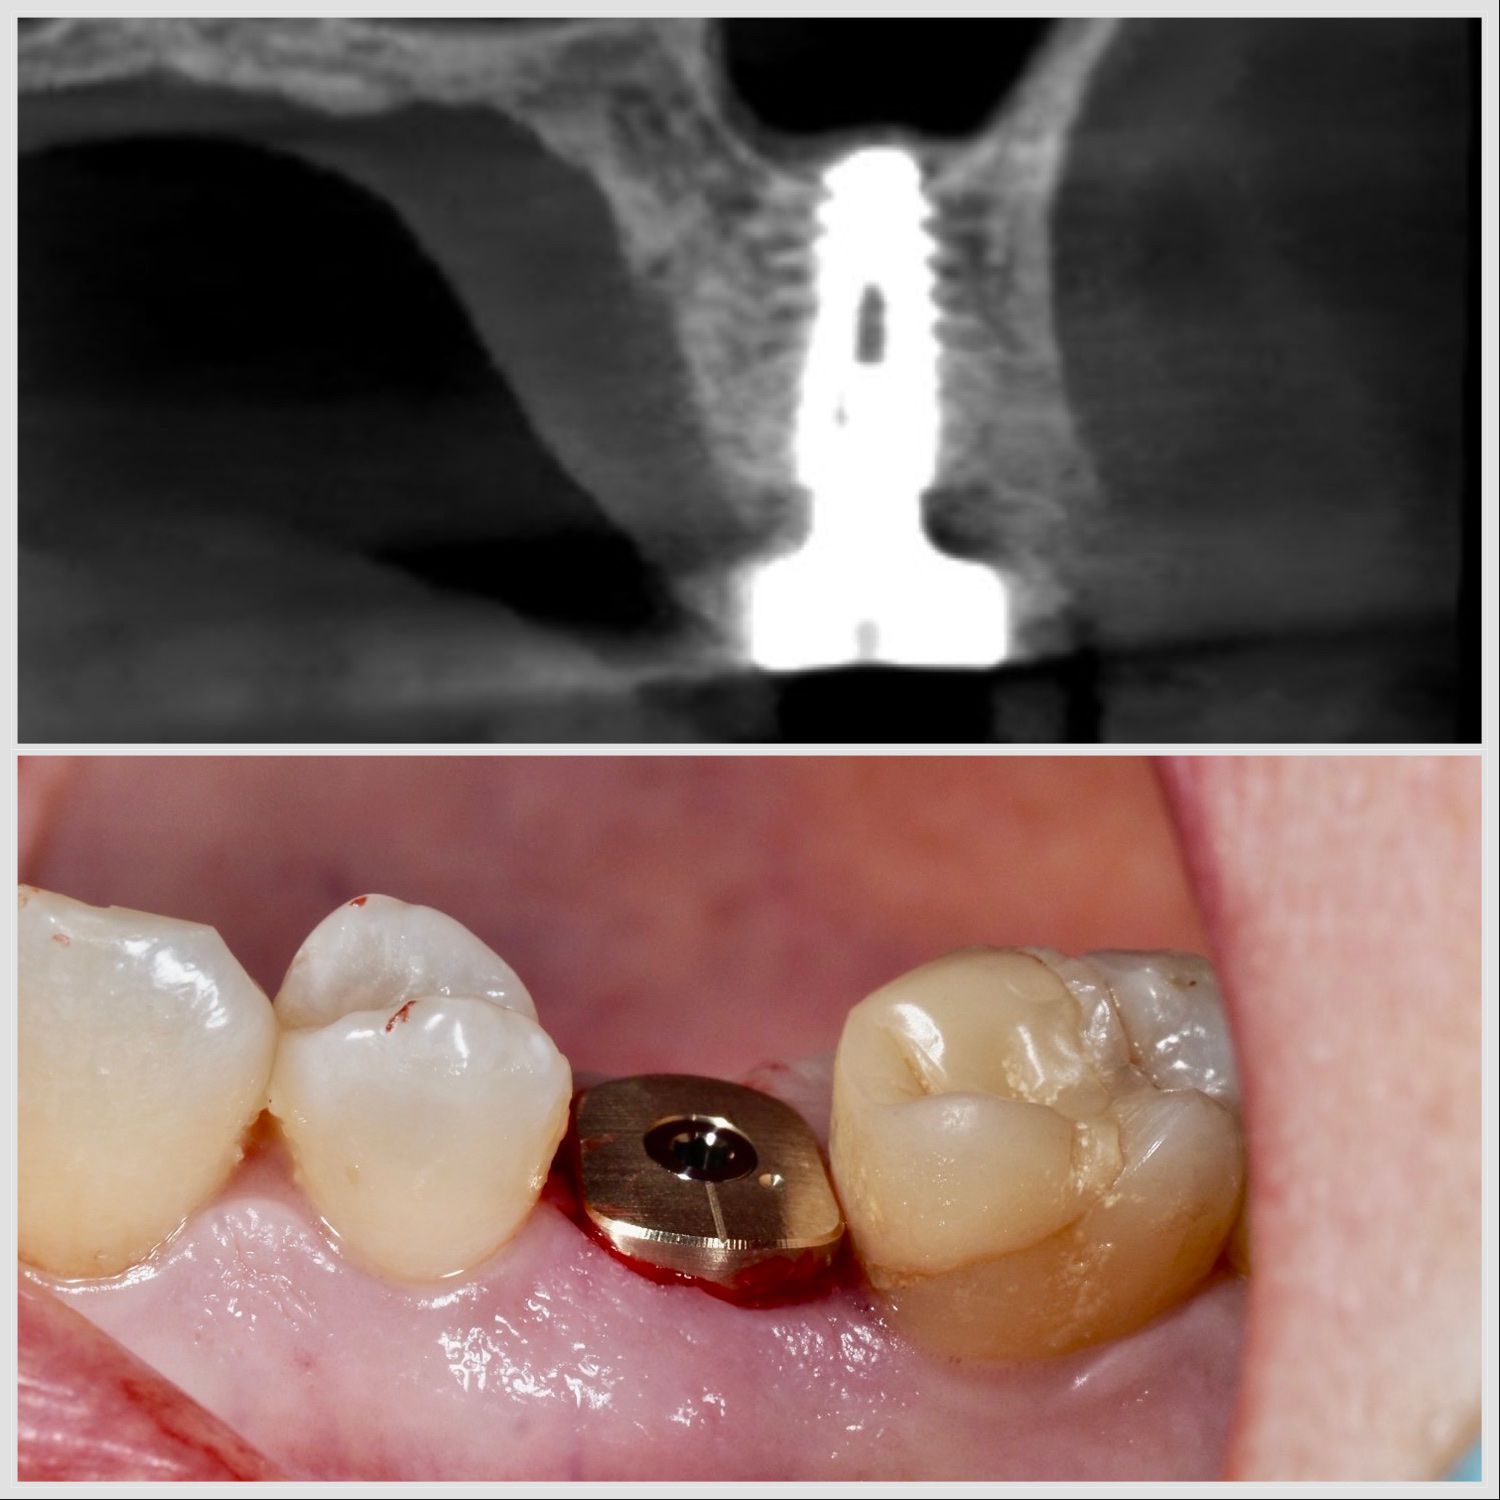

Pose d’un implant selon la technique Summers avec élévation du sinus par voie crestale à Apolline Dental Care à Corbeil-Essonnes

Implant Summers Pilier Anatomique